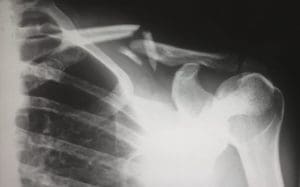

Una fractura menor sanará en aproximadamente seis semanas – pero muchos huesos rotos provocan daños a largo plazo, riesgos asociados con infecciones graves que son difíciles de resolver y discapacidades permanentes.

El tobillo, el hombro, la rodilla, el cuello y la cadera, cuando estos sufren daños se afecta la movilidad, se produce dolor e incomodidad a largo plazo, además de afectar la capacidad de disfrutar de la vida. Un reclamo o demanda presentada debe reflejar el impacto en la vida futura de la víctima.